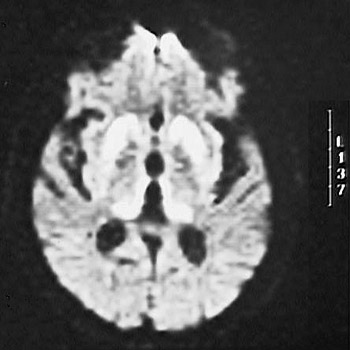

| This cerebral MRI scan demonstrates hyperintensity in the region of the basal ganglia and caudate bilaterally. This is a finding that, in association with a history of a rapidly progressive dementia with myoclonus and electroencephalographic changes of slow waves with spikes, suggests Creutzfeldt-Jakob disease (CJD). |